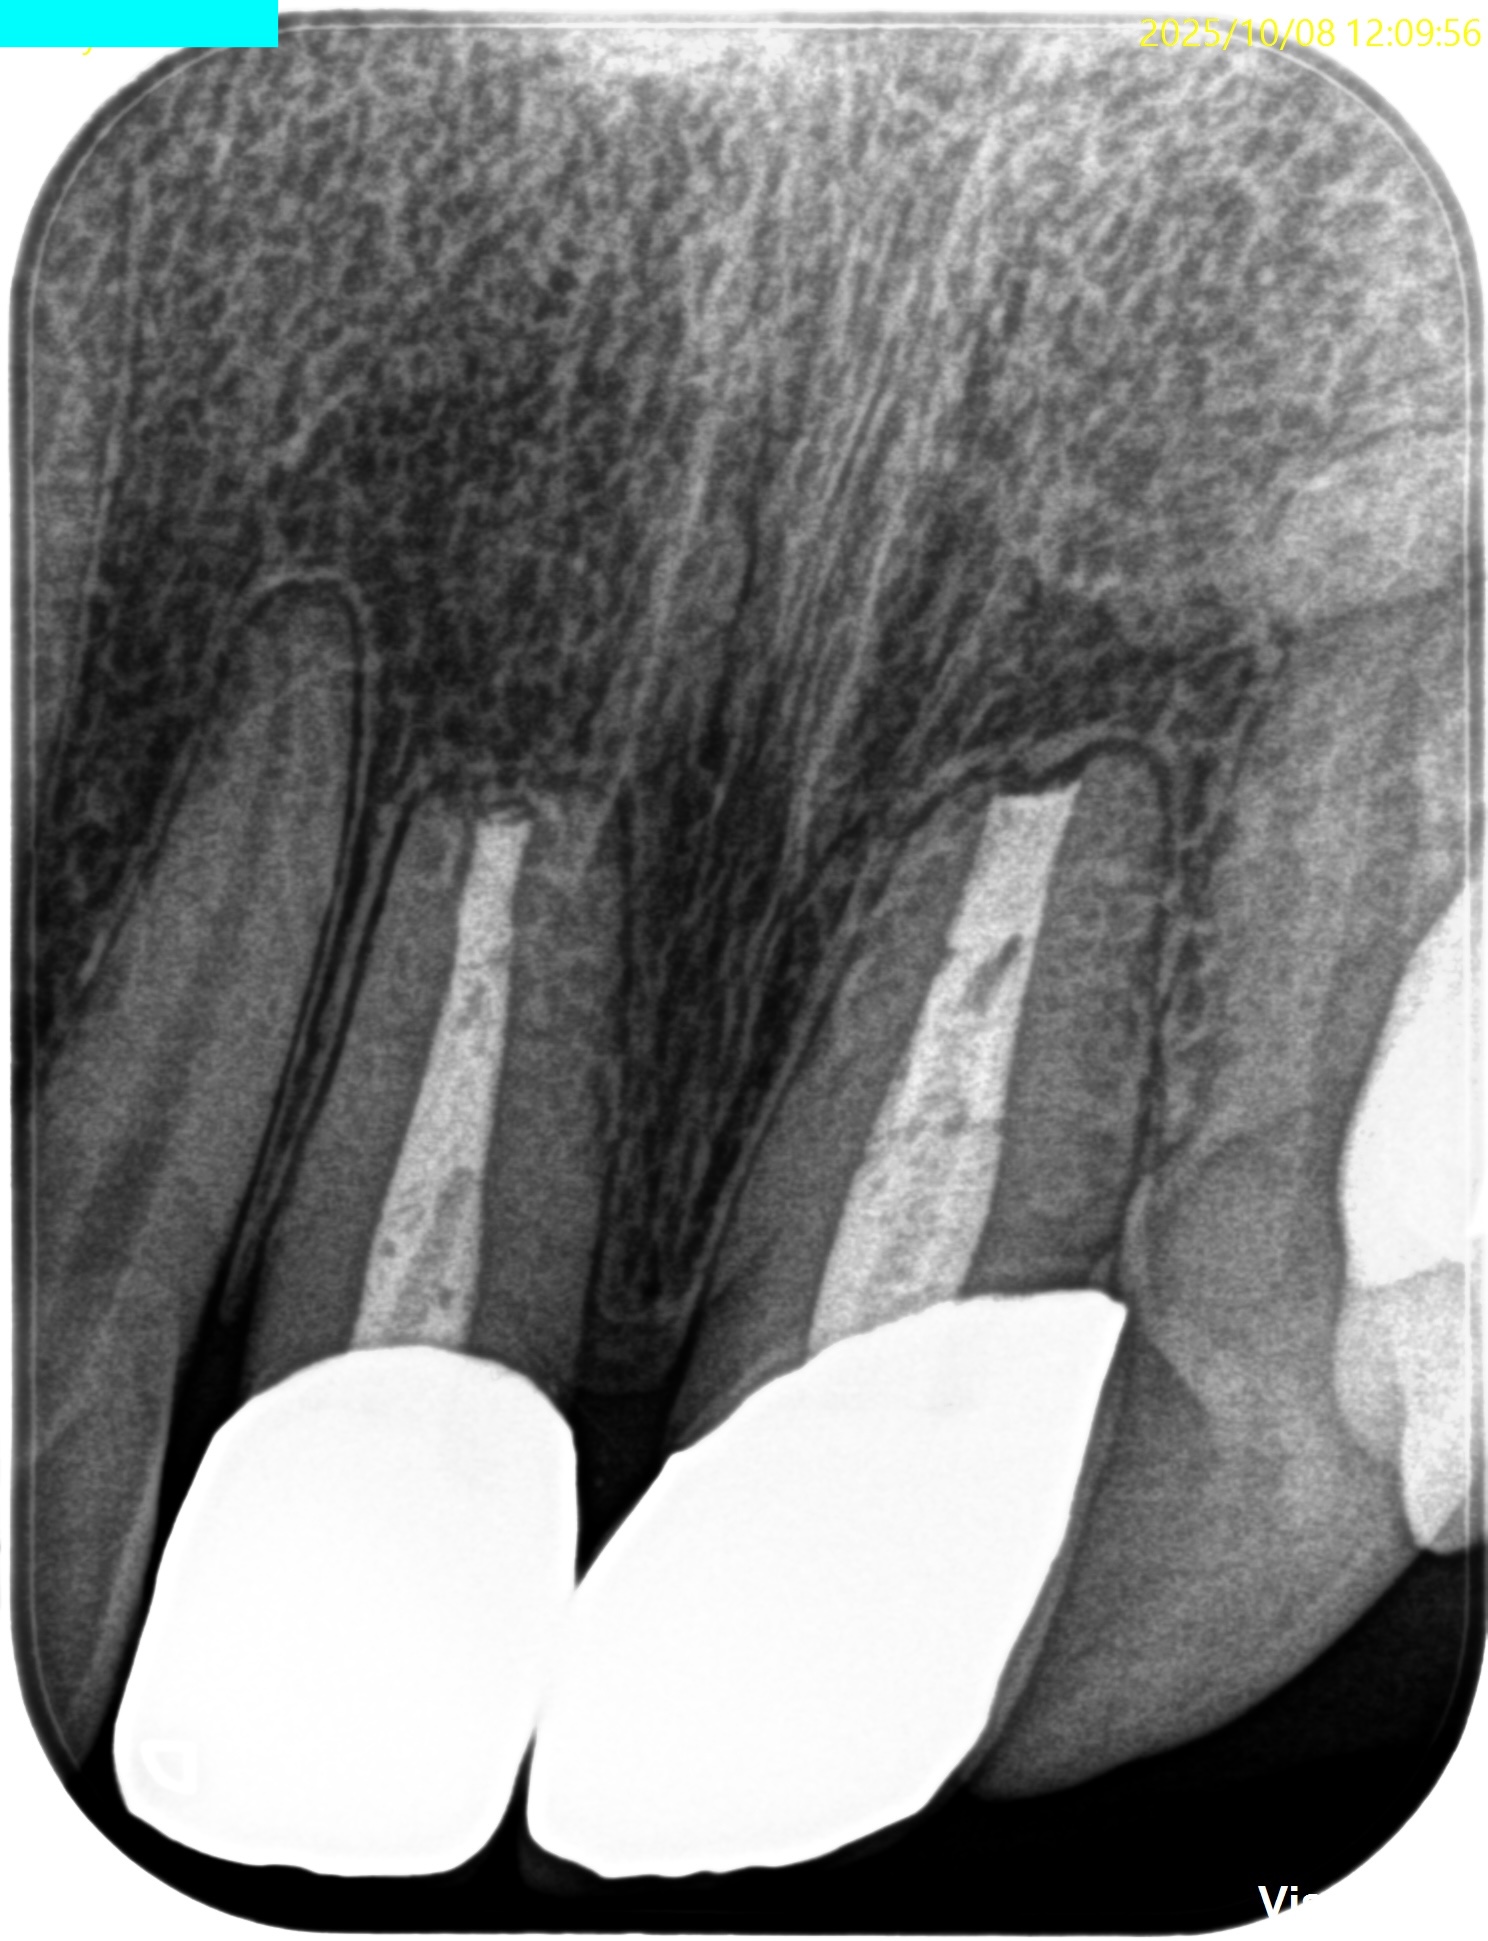

#8,9 Apicoectomy 1yr recall(2025.10.8)

#8

#9

術後と比較した。

術前の問題は消失した。

#9はやはり術前の予想通り1mmの切断で事足りた。